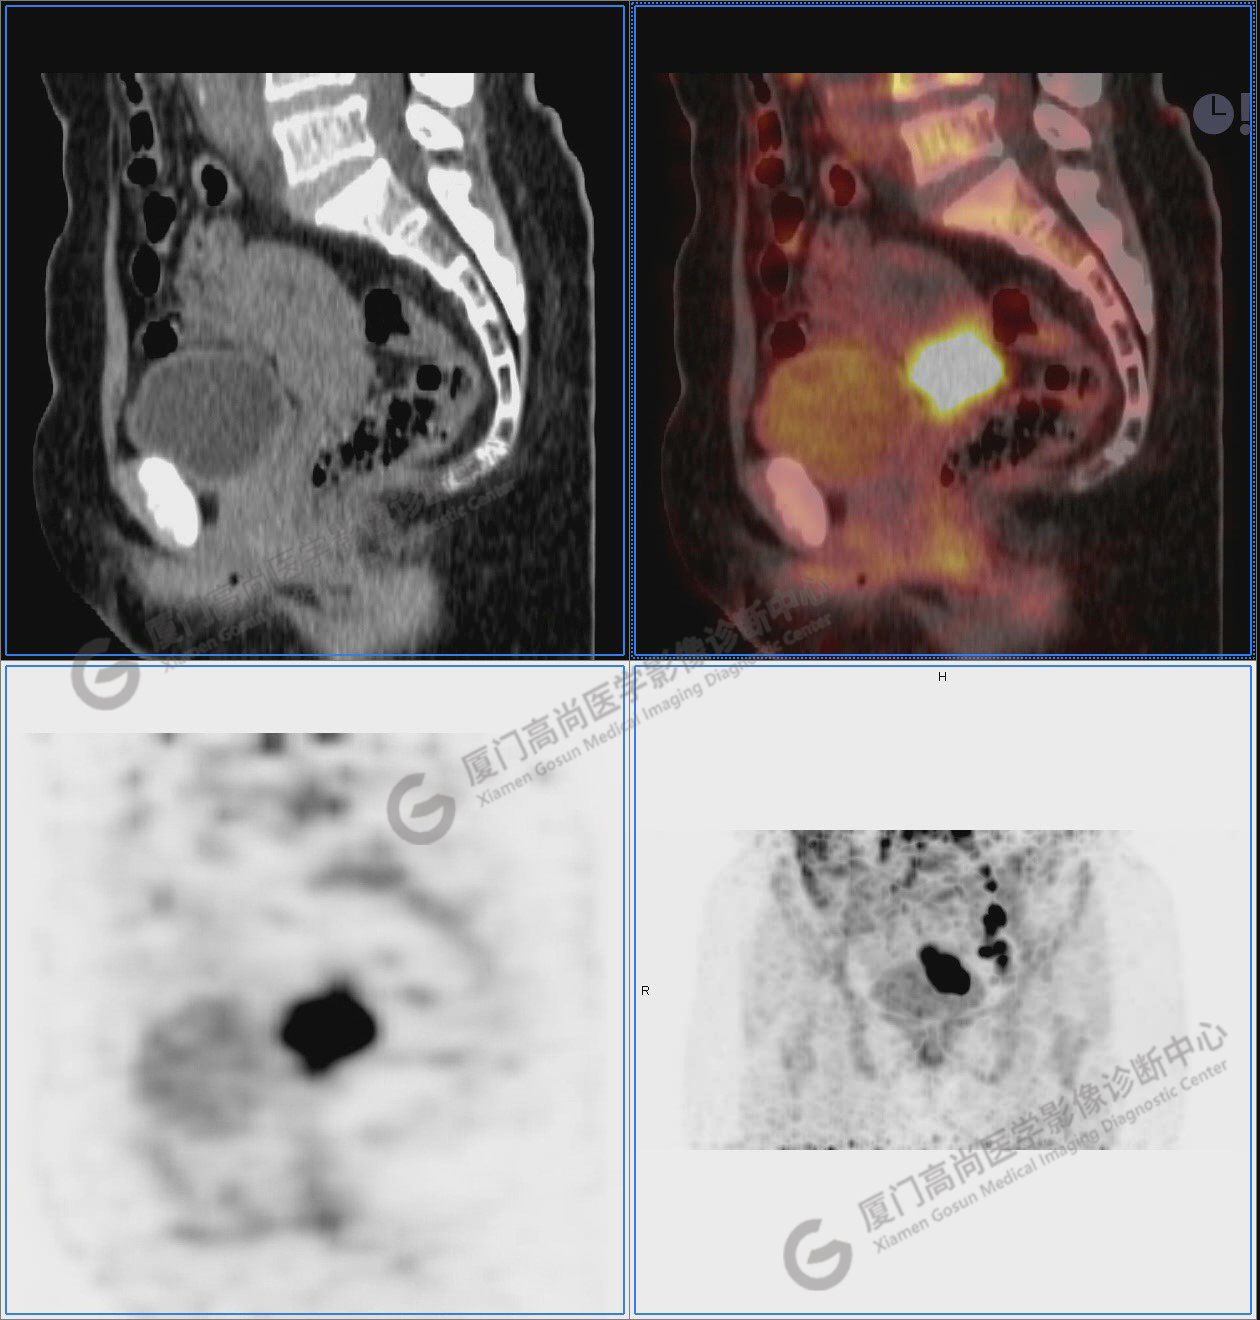

圖10-11:子宮頸軟組織腫塊,代謝異常增高,考慮為宮頸癌。

圖10

圖11

圖12-13:延遲2小時后,宮頸腫塊糖代謝進一步增高。

圖12

圖13